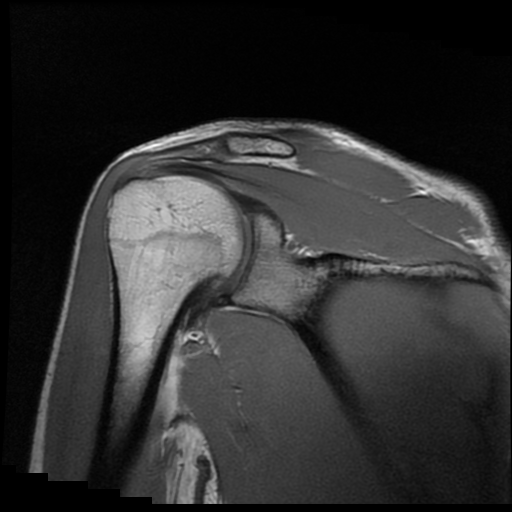

TECNICA EMPLEADA

Se coloca al paciente en decúbito supino, utilizando bobina dedicada de 8 canales, obteniendo imágenes en planos axial, sagital y coronal, secuencias, Spin Echo, Eco de Gradiente, potenciadas a Densidad de Protones, con pulsos de saturación de grasa.

HALLAZGOS IMAGENOLOGICOS

Lesión post traumática de Hill Sachs a nivel de la cabeza humeral, tendinosis aguda del supra espinoso.